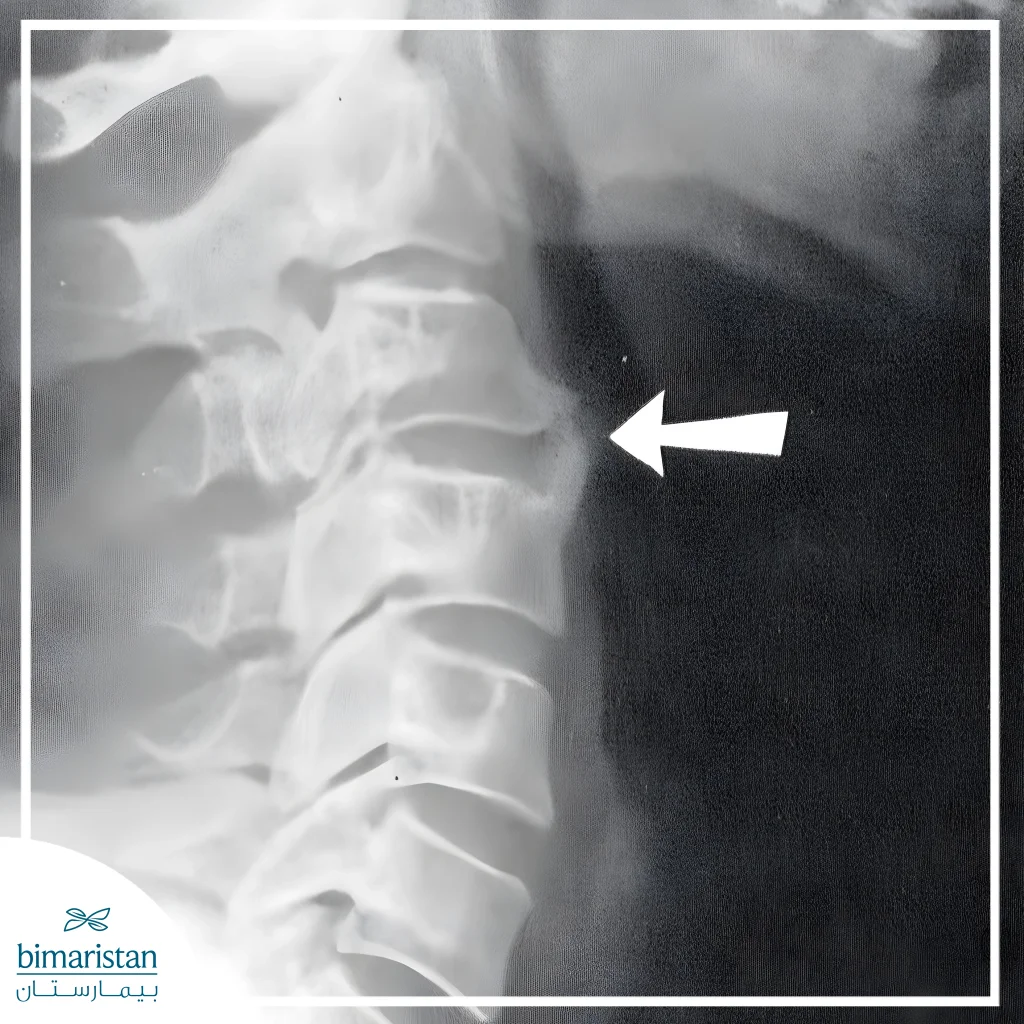

X-ray

X-rays are one of the most common ways to detect bone spurs, showing the size and shape of the spur and how it affects the stability of the spine. X-rays can also follow the progression of the condition over time and make sure there are no sudden changes in the vertebrae.

Normal and pathological protrusions can be distinguished through medical imaging such as X-rays or MRI, which show the size and shape of the protrusion and its impact on the nerves. Early intervention improves outcomes and reduces complications significantly.